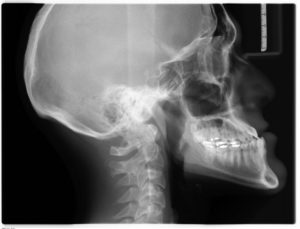

Røntgenundersøgelse

04 august 2025